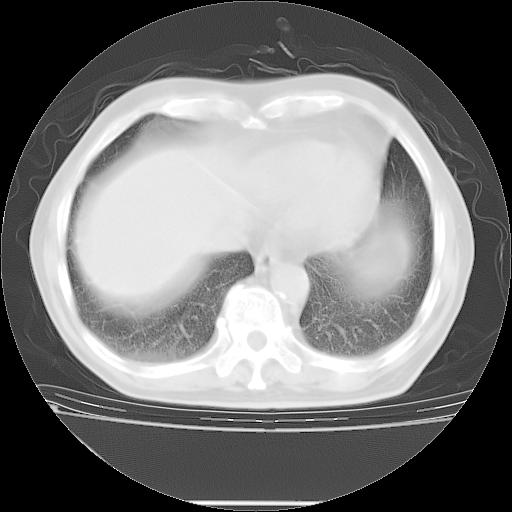

今天复查肺部CT,发现双肺广泛磨玻璃样改变。所以我把3月19日和5月9日相隔50天的肺部CT上传。请大家会诊。

2009年3月19日肺部CT片。

2009年3月19日肺部CT